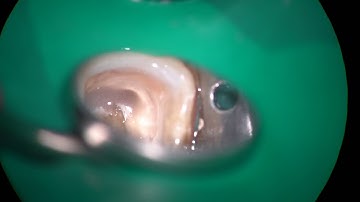

Ledge-bypassing technique/レッジバイパス法